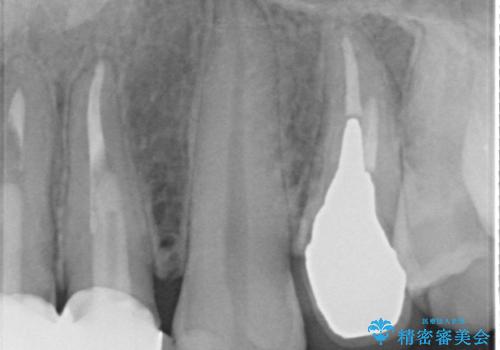

左上4の補綴物を除去したところ縁下歯質だったため、歯牙の挺出を提案し行いました。

縁下カリエス(歯茎より深い虫歯)の治療について

虫歯が進み歯茎より深くなってしまうと、虫歯を取り残してしまうリスク、樹脂の硬化の妨げ、補綴物の不適合、歯肉炎・歯周病のリスクの増大等様々な弊害が起こり得ます。

そのため当院では歯周外科手術(歯茎を下げる手術)や歯の挺出による、虫歯が歯茎より深いという問題の解決を推奨しております。